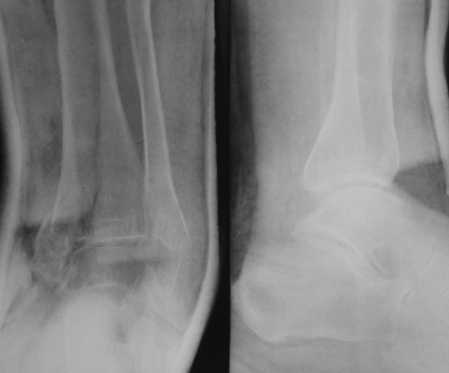

Посмотрели снимки после репозиции - не понравилась зона синдесмоза.

Сделали 3/4-е - впечатление, что в 99-том там что-то было. На

5.11.09г. запланирована КТ.

Косая после репозиции.JPG

79KB (81487 bytes)